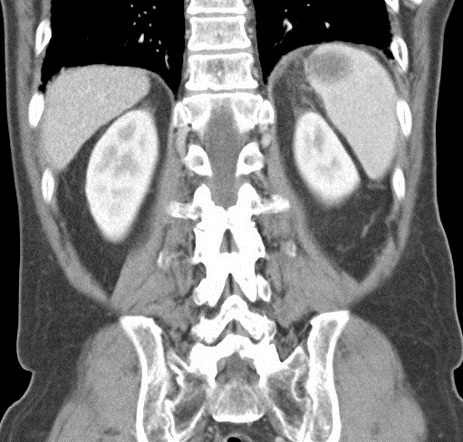

Image radiologique TDM en coupe coronal de

adenopathie peripherique , peri-splenique ,

peri-coeliacque ou mesenterique d'une lymphome maligne de la rate peu être s'observer |